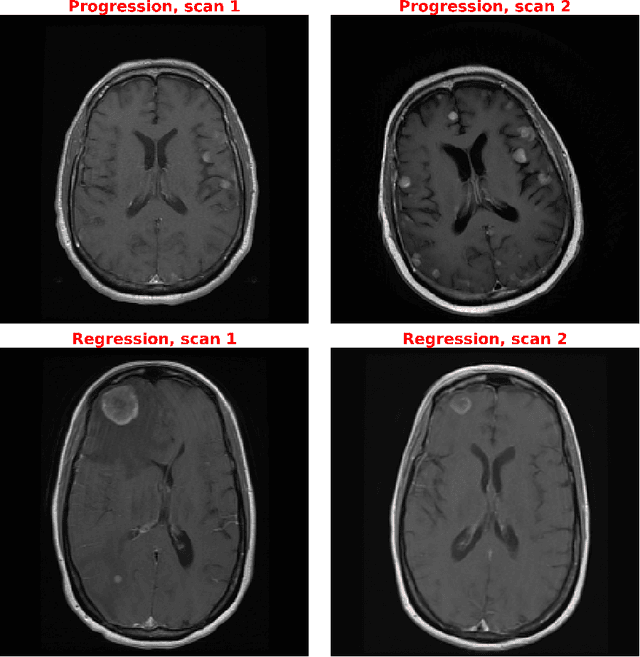

Abstract:Purpose: A core component of advancing cancer treatment research is assessing response to therapy. Doing so by hand, for example as per RECIST or RANO criteria, is tedious, time-consuming, and can miss important tumor response information; most notably, they exclude non-target lesions. We wish to assess change in a holistic fashion that includes all lesions, obtaining simple, informative, and automated assessments of tumor progression or regression. Due to often low patient enrolments in clinical trials, we wish to make response assessments with small training sets. Deep neuroevolution (DNE) can produce radiology artificial intelligence (AI) that performs well on small training sets. Here we use DNE for function approximation that predicts progression versus regression of metastatic brain disease. Methods: We analyzed 50 pairs of MRI contrast-enhanced images as our training set. Half of these pairs, separated in time, qualified as disease progression, while the other 25 images constituted regression. We trained the parameters of a relatively small CNN via mutations that consisted of random CNN weight adjustments and mutation fitness. We then incorporated the best mutations into the next generations CNN, repeating this process for approximately 50,000 generations. We applied the CNNs to our training set, as well as a separate testing set with the same class balance of 25 progression and 25 regression images. Results: DNE achieved monotonic convergence to 100% training set accuracy. DNE also converged monotonically to 100% testing set accuracy. Conclusion: DNE can accurately classify brain-metastatic disease progression versus regression. Future work will extend the input from 2D image slices to full 3D volumes, and include the category of no change. We believe that an approach such as our could ultimately provide a useful adjunct to RANO/RECIST assessment.